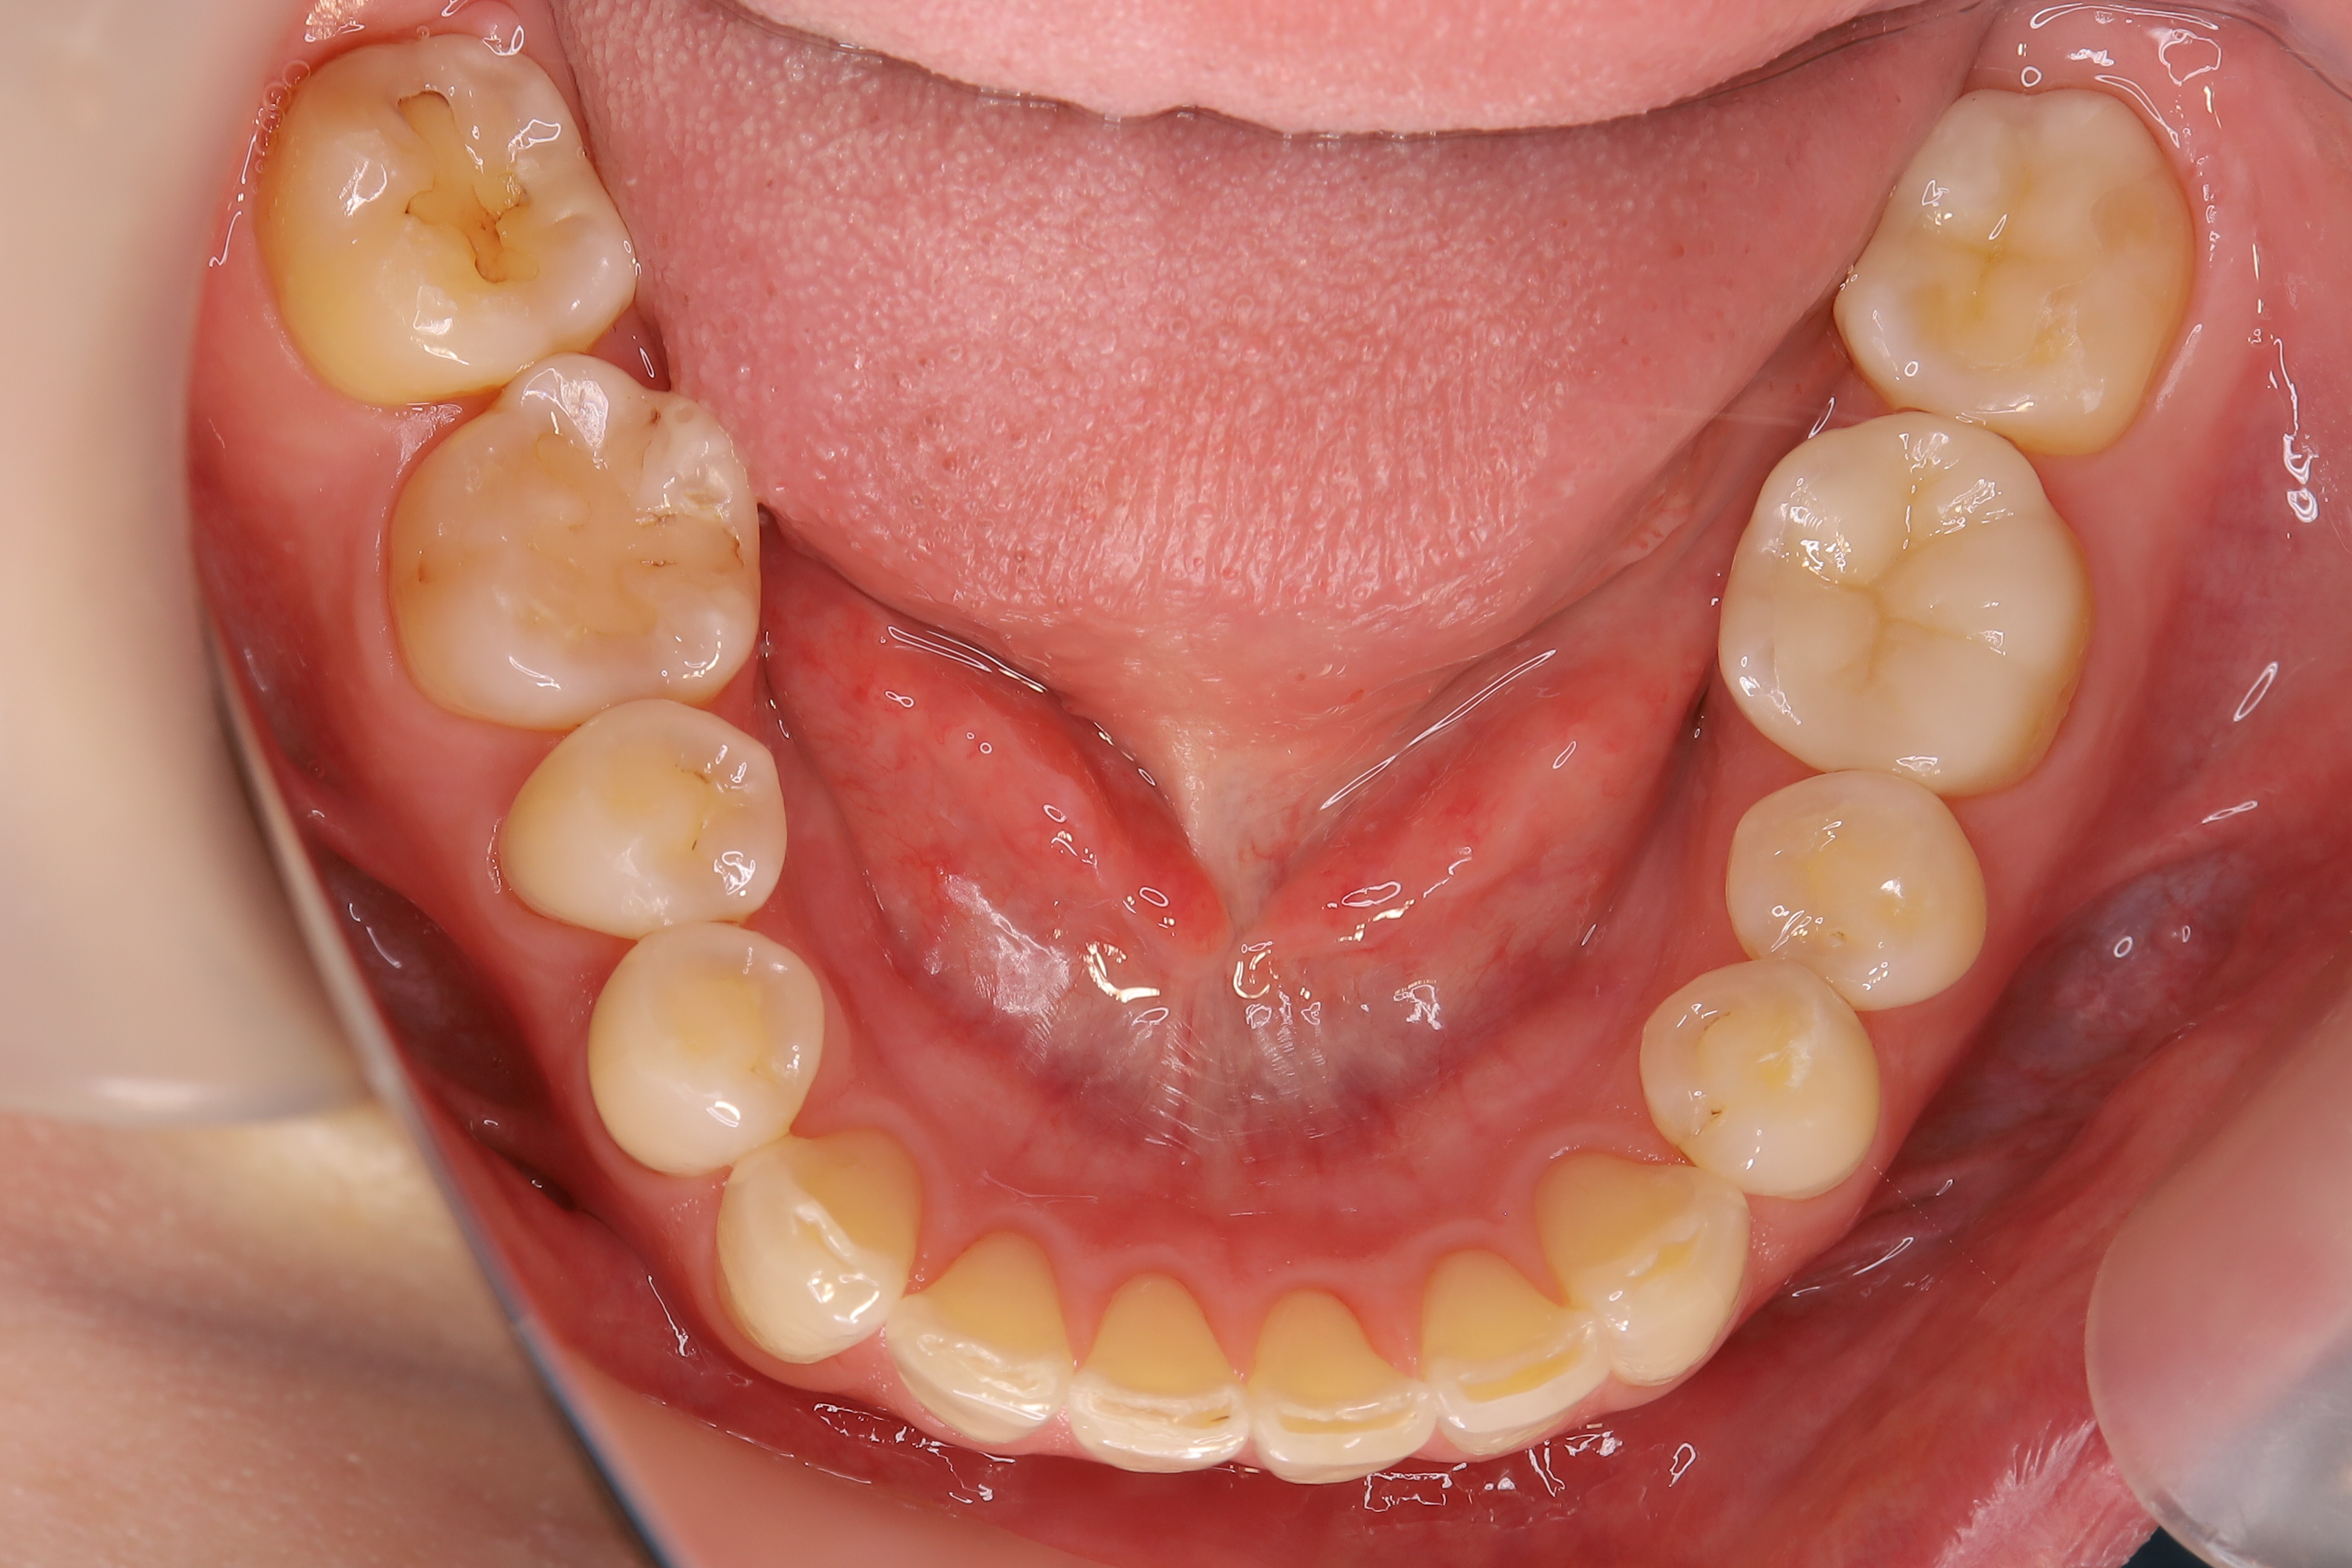

審美歯科治療

症例紹介